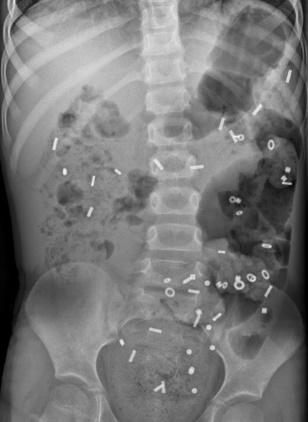

- Röntgenfoto van de buik: Hiermee kan worden bekeken hoe ernstig de verstopping is. Soms wordt dit gecombineerd met een markerstudie, waarbij uw kind capsules inneemt om de snelheid van de ontlasting te meten.

Coloninloop: Dit is een onderzoek waarbij contrastvloeistof via het poepgat wordt ingebracht om de dikke darm beter te bekijken. Daarna worden er een aantal röntgenfoto's na elkaar gemaakt, zodat de darm goed te zien is. Zo kan de arts goed beoordelen of de darm lang, wijd of kronkelig is.- Als uw kind dit spannend vindt, kan een medisch pedagogisch zorgverlener u en uw kind helpen om ervoor te zorgen dat dit proces zo soepel mogelijk verloopt.